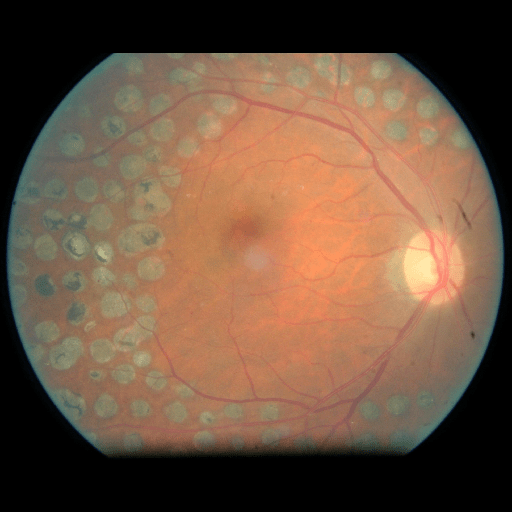

We conducted a case study on diagnosing diabetic retinopathy with ensembles of DL models. For benchmarking the performance of our ensemble-based solutions under the scheme described in Sec.3.3, we used two popular collections of diabetic retinopathy image data, the Kaggle Diabetic Retinopathy dataset [22] (hereafter referred to as “Kaggle-DR”) and the Messidor-2 dataset [23], each respectively consisting of and high resolution images. Diabetic retinopathy is graded into five SLs, as displayed in Figure 2. Following the problem setup used in previous papers [24], we trained models to distinguish the referable (SL2-4) cases from the non-referable ones (SL0 & SL1) (see Section B.1 for more detailed descriptions). We also tested our trained ensemble models on two o.o.d. image datasets (ImageNet [25] and CIFAR-10 [26]) to examine their capabilities of identifying o.o.d. inputs (see Section B in the supplementary materials).

5.1 Distribution of Uncertainty Scores

Distribution of Uncertainty Scores Across Different Severity Levels As explained in Section 3, each uncertainty metric essentially defines an order/ranking among the data points. We conducted an analysis to better understand what data will be assigned high uncertainty under a particular uncertainty metric . Picking out the highest ranked data points (), we calculated the ratio of data points from each SL. Figure 4 summarizes the results as box plots for the Kaggle-DR and the Messidor-2 datasets; additional detailed statistics can be found in Table S.1 in the supplementary materials. From the plot and table, SL1 & SL2 examples account for a higher proportion among the top-ranked uncertain examples across the three ensemble methods. This finding matches our intuition that incipient disease examples (SL1 & SL2) are more likely to be considered uncertain by ensemble methods due to their ambiguity.

In contrast, the MC-dropout method showed the worst overall performance among the three, as it can be seen from the high ratios of SL0 examples among the uncertain negatives in Figure 4. The histograms in Figure 2 provides another perspective to look into the phenomenon, where a decent proportion of MC-dropout model’s predictions on SL0 inputs entailed low confidence (far from 0 or 1), which from another angle explained why MC-dropout was less specific in terms of lower FNP; many no-DR inputs (i.e. SL0) were erroneously assigned high uncertainty by MC-dropout models.

The Kaggle-DR dataset comprises high resolution images. The presence of diabetic retinopathy is rated into five different SLs: no-DR (SL0), mild (SL1), moderate (SL2), severe (SL3), and proliferate (SL4), as illustrated in Figure 2. We divided the Kaggle-DR dataset into a development set and a test set, which respectively consisted of and images. The data in the development set were used to train and validate our Deep Learning (DL) models. The Messidor-2 dataset [38] that consisted of images was also used in our experiment as an additional dataset to test the true generalization performance of the models trained on the Kaggle-DR dataset. Images in Messidor-2 dataset were graded into the five SLs as in the Kaggle-DR dataset. Figure S.1 provides an illustration of the datasets used in our experiments.